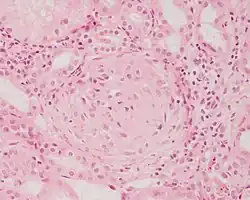

Photomicrograph of a kidney biopsy from a person with crescentic glomerulonephritis showing prominent fibrocellular crescent formation and moderate mesangial proliferation in a glomerulus. Hematoxylin and eosin stain. | |

Rapidly progressive glomerulonephritis, also known as crescentic GN, is characterised by a rapid, progressive deterioration in kidney function. People with rapidly progressive glomerulonephritis may present with a nephritic syndrome. In management, steroid therapy is sometimes used, although the prognosis remains poor.[9] Three main subtypes are recognised:[4]: 557–558

Histopathologically, the majority of glomeruli present "crescents". Formation of crescents is initiated by passage of fibrin into the Bowman space as a result of increased permeability of glomerular basement membrane. Fibrin stimulates the proliferation of endothelial cells of Bowman capsule, and an influx of monocytes. Rapid growing and fibrosis of crescents compresses the capillary loops and decreases the Bowman space, which leads to kidney failure within weeks or months.